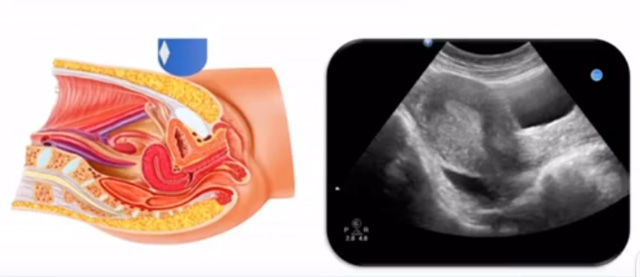

女性生殖系統(tǒng)包括內(nèi)、外生殖器官及其相關組織以及鄰近器官,其中內(nèi)生殖器是我們超聲檢查的主要對象。那么內(nèi)生殖器包括陰道、子宮還有輸卵管及卵巢。輸卵管及卵巢稱為子宮附件。子宮是倒置梨形,但是它是空腔厚壁肌性器官。它的正常值在育齡婦女。超聲探頭放在貼近腹壁盆腔上面位置,來看這個子宮在超聲上面的表現(xiàn)。從輪廓上來講,和示意圖是一樣的。這就是在超聲上面顯示的一個子宮的圖片。子宮在不同的時期與子宮頸的比例。成年婦女指的是育齡婦女為2:1子宮體是比較大的,嬰兒期為1:2說明宮頸比較大,絕經(jīng)期1:1。所以我們在看到子宮圖時候可以根據(jù)宮體宮頸比例大致可以推測屬于哪個時期的婦女。另外還可以根據(jù)比例大小來推斷是一個正常子宮還是異常子宮。

子宮從外到內(nèi),漿膜層、肌層、粘膜層。宮體部宮頸為梭形結(jié)構(gòu)。宮腔為上寬下窄的三角形,連接為峽部。子宮有什么功能呢?月經(jīng)血產(chǎn)生跟排出通道,精子運行通道受精作用。囊胚著床及胎兒發(fā)育、生長的場所。分娩時產(chǎn)生宮縮使胎兒、胎盤娩出。未孕的子宮是很小的,已孕子宮就非常大,平均胎兒都有6斤重。所以這個后壁就體現(xiàn)出來。輸卵管由子宮角部向外延伸,為一對細長而彎曲的管道,呈管狀中空結(jié)構(gòu),大概長度是8-14厘米,粗1-4毫米,它的下方為卵巢和闊韌帶。間質(zhì)部是厚一點的,峽部是比較窄的地方,壺腹部,漏斗部。正常情況下,輸卵管在普通超聲DR難以顯示。